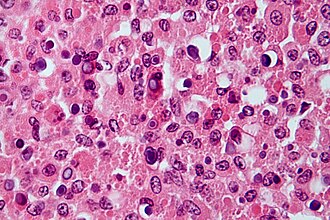

Malakoplakia with numerous Michaelis-Gutmann bodies. H&E stain. | |

| LM | basophilic calcified bodies approximately the size of a RBC (Michaelis-Gutmann body) - inside or outside of macrophages, large foamy macrophages with granular cytoplasm +/- multinucleation, lymphocytes |

- Basophilic calcified lysosomes (Michaelis-Gutmann bodies) -- key feature.

- May be inside or outside of macrophages - often size of RBC or larger.

- Large foamy macrophages with granular cytoplasm.

- Occasional multinucleated giant cell.

- Lymphocytes.